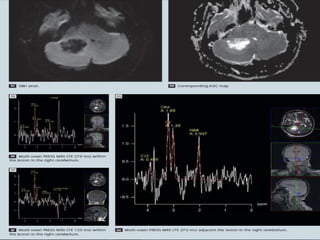

A 52-year-old male with high grade tumor (glioblastoma, WHO grade IV) was

misdiagnosed as low grade tumor due to nonspecific MRS pattern and too small number

of VOIs. A and B, T2 high signal intensity lesion is noted in the right hippocampus and

anterior temporal lobe without definite contrast enhancement (A: T2-weighted image,

B: postcontrast T1-weighted image). C and D, MR spectroscopy of the mass shows slightly

increased choline, interpretating as low grade tumor.